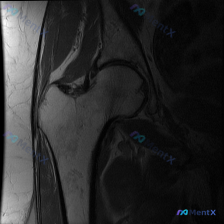

这个髋关节MRI显示的盂唇信号异常,更像撕裂还是退变?

看到一个髋关节MRI病例,单幅冠状位T2加权像显示髋臼外上缘盂唇有局灶性高信号改变。正常情况下,盂唇在T2加权像上应该是低信号的。大家看看这个高信号更可能是盂唇撕裂还是退变?还需要补充哪些序列的图像来明确诊断?